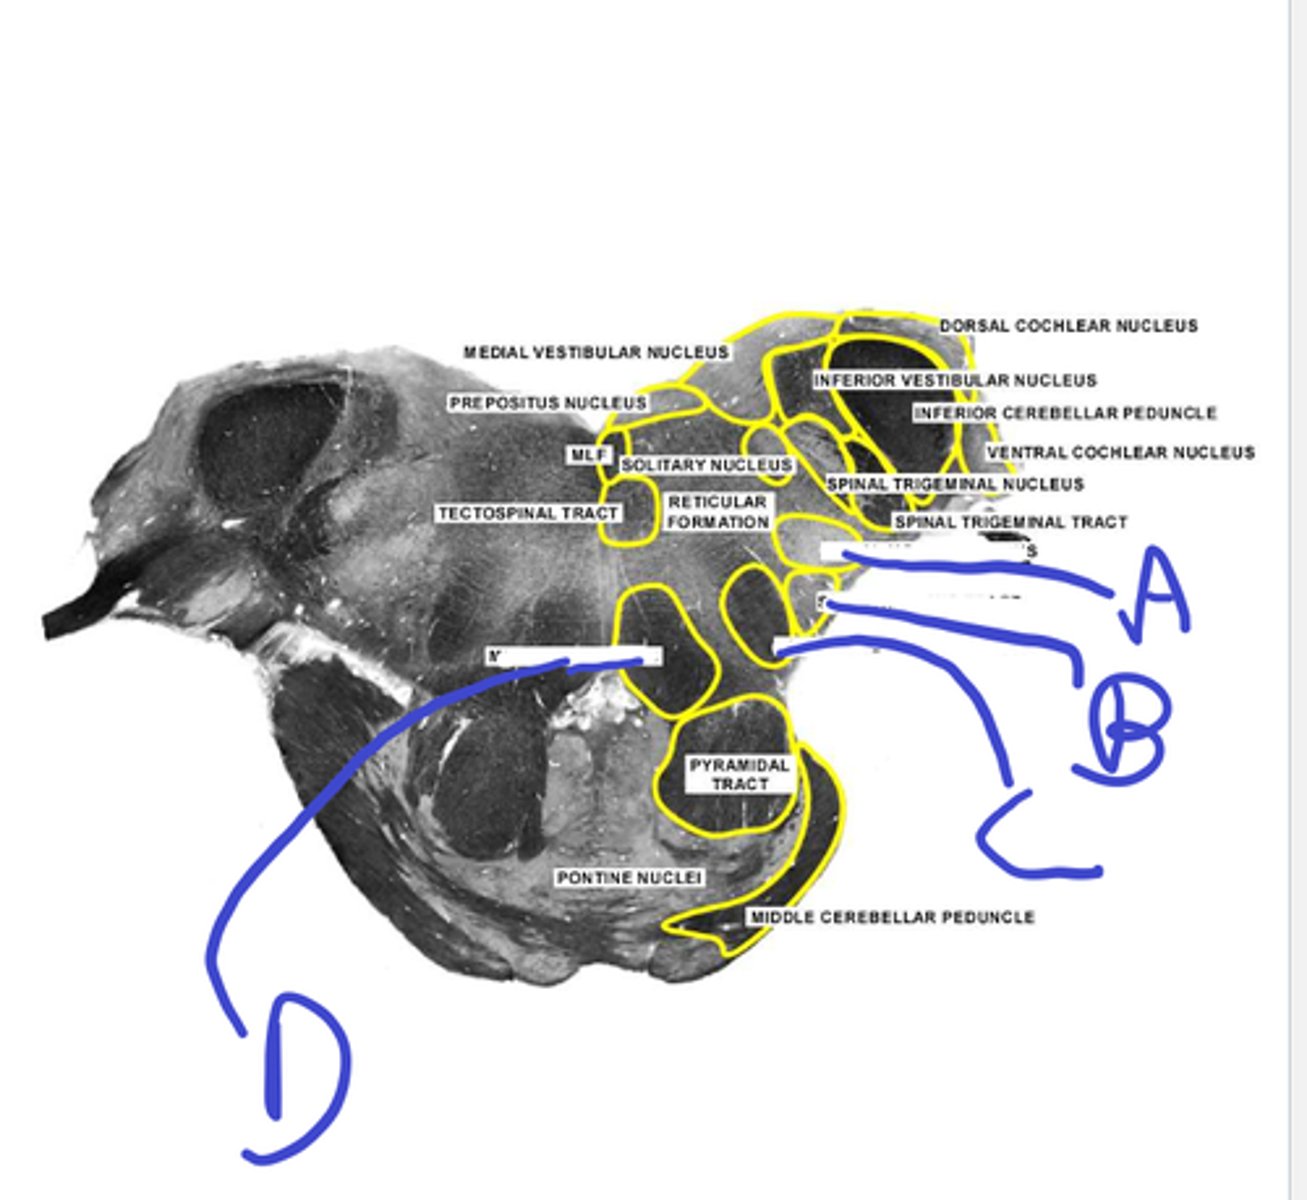

a-med vestibular nuc

b-dorsal cochlear nuc

c-inf vestibular nuc

d-ventral cochlear nuc

e-inf cerebellar peduncle

abcde

f-spinotrigeminal tract/nuc

g-solitary nuc

h- mlf is one circle dorsal

i-medial lemniscus

j-inf olive

fghij

k- spinothalamic

l-central tegmental tract

m-pyr tract

n-pontine nuc

o-reticular formation

klmno